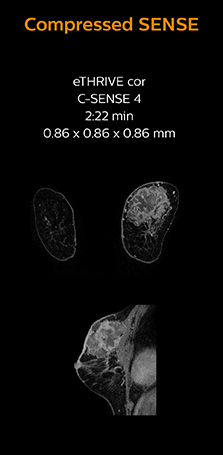

“Compressed SENSE has allowed us to increase spatial resolution in breast MRI, which benefits our diagnostic confidence”

Identification of small breast lesions requires high resolution

Dr. Koyama says that he used to believe that high resolution MRI at 1.5T required long scan times, and SNR was low. “With Compressed SENSE, however, it is possible to acquire high quality images, even with higher Compressed SENSE factors, so in a quite short time.”

“In breast scanning, high resolution is important to help me identify very small mammary lesions, so, we need high spatial resolution in 2D T1- and T2-weighted images, as well as a short scan time. Compressed SENSE has allowed us to increase spatial resolution, which benefits our diagnostic confidence.”

Dr. Koyama says that a C-SENSE factor of 4.0 was chosen to increase their spatial resolution in 3D dynamic breast scanning. “In addition to a high temporal resolution, we also require high spatial resolution, which helps us to see details of the internal structure of the lesion and to see lesions separately from normal anatomic structures. We can also see if a lesion extends into adjacent organs and anatomic structures.”

3D MRI with Compressed SENSE of patient with breast cancer

This patient underwent MRI on Ingenia 1.5T with Compressed SENSE. Compressed SENSE was used to reduce the scan time in order to decrease the time that the patient may experience discomfort and pain, both of which may lead to patient motion. The 3D BreastVIEW and 3D high resolution mDIXON images – both mDIXON contrasts are acquired in the same exam – show high quality images even with the shorter scan time. The spatial resolution of the dynamic scan with Compressed SENSE is higher than in the previous protocol (not shown) which allows for better visualization of the lesion with respect to the muscles of the thoracic wall and better delineation of small structures.

For breast imaging, a fast, high resolution scan can be important for a female patient having to lie in an uncomfortable, face-down position in the scanner. Compressed SENSE also helps us to obtain higher1 quality images using 3D BreastVIEW and 3D high resolution mDIXON sequences in the same examination time as in our previous exam protocol.